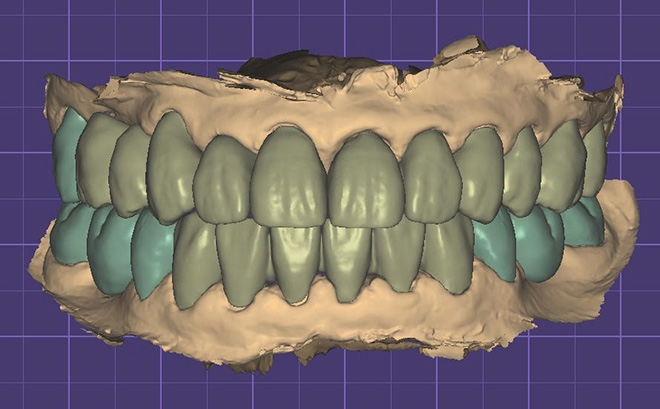

治療中のデジタルデータ

患者様は50代女性、治療期間は1年。

この症例の治療費

奥歯スタンダードインプラント4本→1,760,000円(税込)

《インプラント1本あたり440,000円(税込)》

セラミック20本→2,640,000円(税込)

《セラミック1本あたり132,000円(税込)》

咬合再構成(全ての仮歯と噛み合わせ治療)→792,000円(税込)

総額5,192,000円(税込)

この症例のリスク

治療中の仮歯が外れたり壊れたりすることがあります。

インプラントが稀に脱落することがあります。

セラミックが稀に欠けたり割れたりする可能性があります。